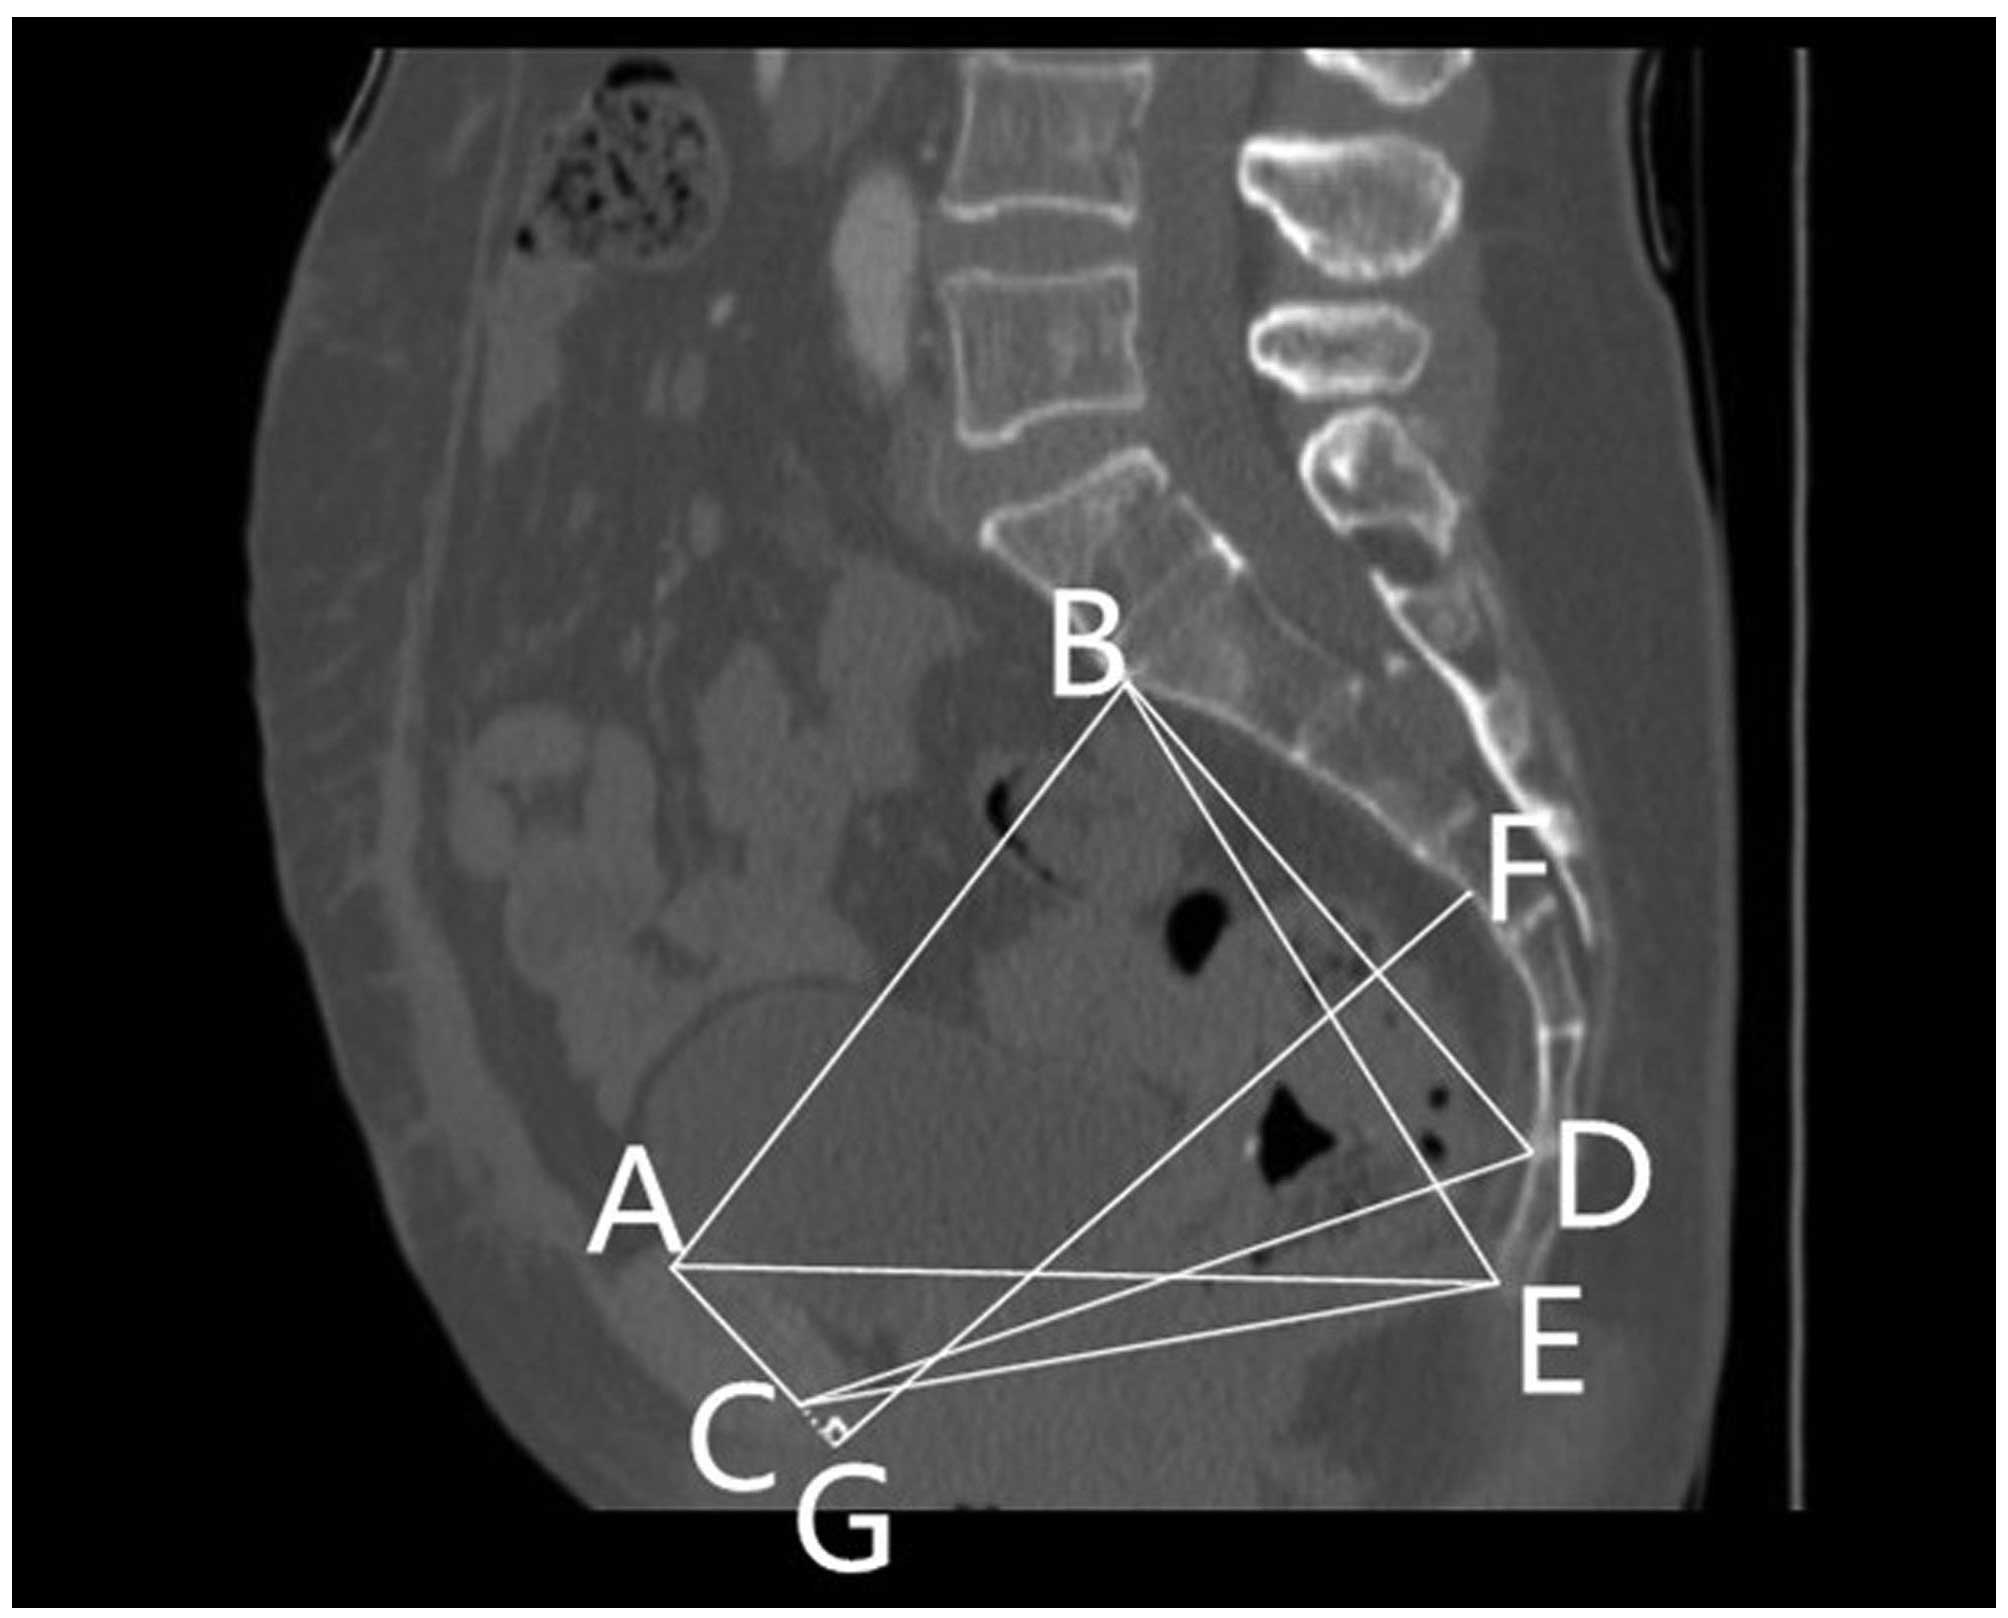

1. Anteroposterior diameter of the pelvic inlet (AB): A line from the superior median aspect of the pubic symphysis to the sacral promontory.

2. Anteroposterior diameter of the mid-pelvis (CD): A line from the inferior median aspect of the pubic symphysis to the sacrococcygeal junction.

3. Anteroposterior diameter of the pelvic outlet (CE): A line from the inferior median aspect of the pubic symphysis to the tip of the coccyx.

6. The height of the pubic symphysis (AC).

7. The sacrococcygeal distance (BE): Distance from the sacral promontory to the tip of the coccyx.

8. The sacral distance (BD): Distance from the sacral promontory to the sacrococcygeal junction.

9. Sacrococcygeal-pubic angle (α): The angle between an extension of the line forming the anteroposterior diameter of the pelvic inlet and that of the anteroposterior diameter of the pelvic outlet.

10. Sacropubic angle (β): The angle between an extension of the line forming the anteroposterior diameter of the pelvic inlet and that of the anteroposterior diameter of the mid-pelvis.

13. Diameter of the upper pubis to the coccyx (AE): A line from the superior median aspect of the pubic symphysis to the tip of the coccyx.

14. Sacropubic distance (FG): A perpendicular line from the deepest portion of the sacrococcygeal hollow to the height of the pubic symphysis or an extension of this line.

Figs. 1 and 2 outline the mid-sagittal view of the pelvis in a female patient. Fig. 3 outlines the axial section, showing the interspinous diameter of the mid-pelvis. Fig. 4 outlines the axial section, showing the intertuberous diameter of the pelvic outlet. The relevant measurements are indicated in Figs. 1–4. Assessment of intraobserver error was conducted as detailed in the statistics section.

Figure 1.

Mid-sagittal view of the pelvis in a female patient, indicating pelvic dimensions. (AB) Anteroposterior diameter of the pelvic inlet. (CD) Anteroposterior diameter of the mid-pelvis. (CE) Anteroposterior diameter of the pelvic outlet. (AC) Height of the pubic symphysis. (BE) Sacrococcygeal distance. (BD) Sacral distance. (AE) Diameter of the upper pubis to the coccyx. (FG) Sacrcopubic distance. (A) The superior median aspect of the pubic symphysis. (B) The anterior median aspect of the sacral promontory. (C) The inferior median aspect of the pubic symphysis. (D) The anterior median aspect of the sacrococcygeal junction. (E) The inferior median aspect of the tip of the coccyx. (F) The deepest portion of the sacral hollow or sacrococcygeal hollow. (G) A point of the perpendicular line from the deepest portion of the sacrococcygeal hollow to the height of the pubic symphysis or an extension of this line.